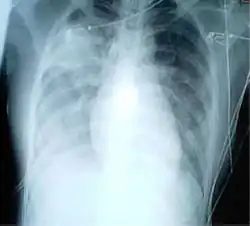

Průběh

Inkubační doba SARS, tj. časový interval, který uplyne od nákazy virem k prvním projevům onemocnění, činí 2–8 dní, v některých případech až 10 dní. Infekce začíná obvykle vysokou teplotou (nad 38 °C), bolestmi hlavy, celkovou únavou. Po 2–8 dnech se přidružuje suchý kašel a dýchací obtíže. U většiny postižených se vyvíjí zápal plic. Vysoká smrtnost (téměř 10 %[2]) je přičítána především příliš silné imunitní reakci vyvolané cytokiny (tzv. cytokinová bouře), hlavní roli má přílišná produkce interferonu gama lidskými buňkami.[4] Protilátky jsou detekovatelné i po 17 letech od prodělání nemoci.[5]